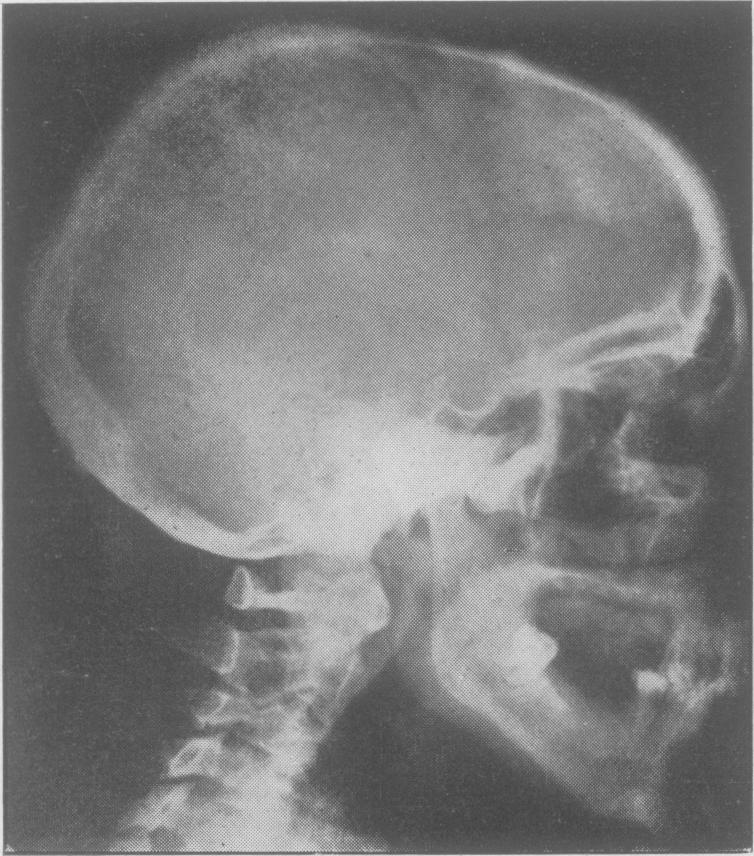

Fibrous dysplasia of bone and comparable conditions in the jaws.

Proc R Soc Med. 1951 Jul;44(7):549-56. doi: 10.1177/003591575104400705.